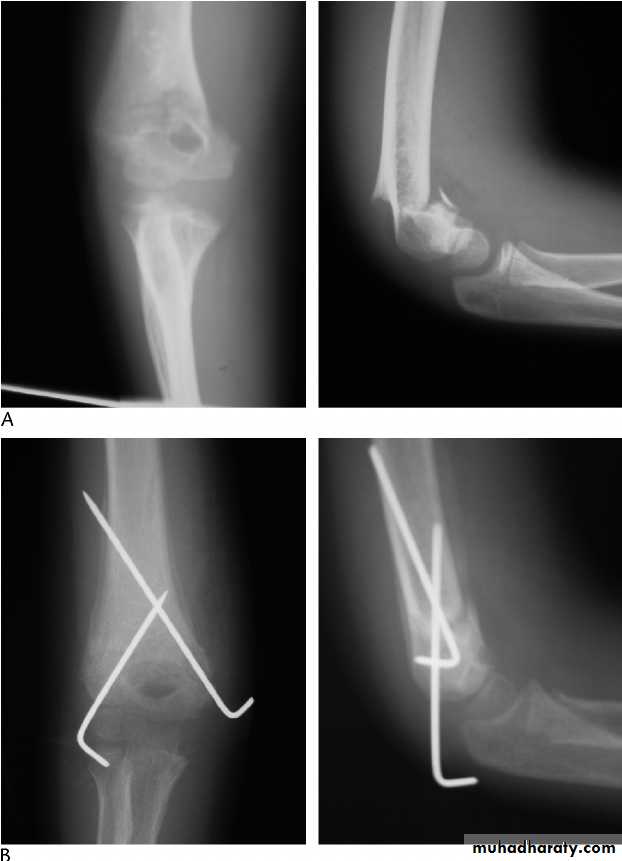

Upper limb

Fall on out stretched hand

Possible complications

Ass n injury

Management

Surgery

complication